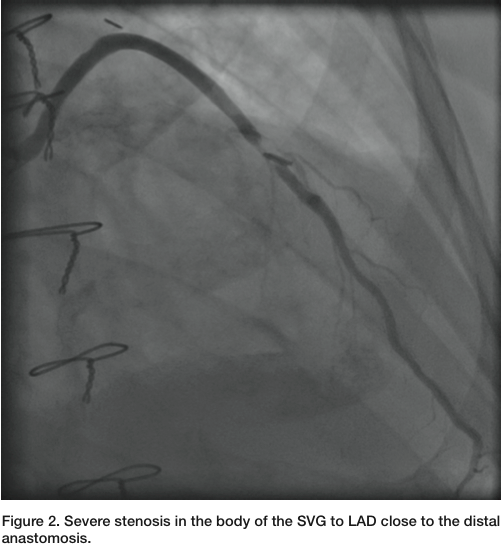

Three months later, the patient presented again with unstable angina. He has been compliant with his clopidogrel and aspirin. He had dynamic ST-T changes, without any elevation of cardiac enzymes. He was brought back to the cardiac catheterization laboratory. Diagnostic images were obtained with Judkins left (JL) 3.5 and Judkins right (JR) 4.0 diagnostic catheters through a 6 French (Fr) Glide sheath (Terumo) access in the right radial artery (RA). The patient had a very tortuous right subclavian and brachiocephalic arteries (Figure 1). The native LAD had a proximal chronic total occlusion. The SVG to LAD demonstrated a patent proximal stent, but with a

90% eccentric focal stenosis in the distal portion of the vein graft, very close to the anastomosis (Figure 2). Weight-based bivalirudin was initiated and a 6 Fr AL1 guide was used to cannulate the SVG to LAD. Though the severe tortuosity caused the cannulation of the graft to be challenging, a very co-axial supportive guide position was achieved (Figure 3, Figure 5). The lesion was crossed with a Kinetix wire (Boston Scientific). Due to the proximity of the lesion to the anastomosis, no distal protection device was deployed. A 3.5mm x 12mm Resolute drug eluting